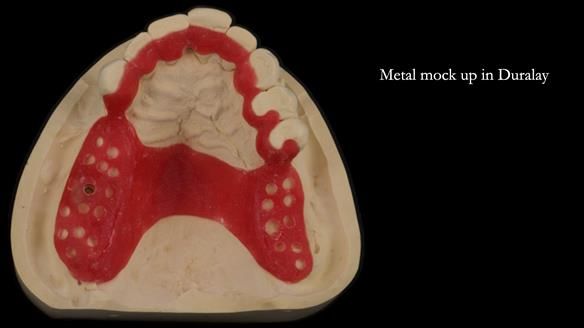

It’s worth saying that the lower denture in this case was made in the early days of Rowan and me using the Scandinavian approach. Rowan cast the metalwork himself for this denture.

Looking back, we would make this denture more hygienic now. The design and finish would be more refined and delicate, particularly when compared with the upper metalwork, which was made later using Chris Hesketh’s chrome work. I will discuss this in detail at the study club.

That said, the lower denture worked beautifully. It did exactly what it was meant to do, even though, by today’s standards, it looks a little agricultural.

A metal-based upper RPD was made,

with metal backings incorporated to future-proof the design

should further teeth fail.